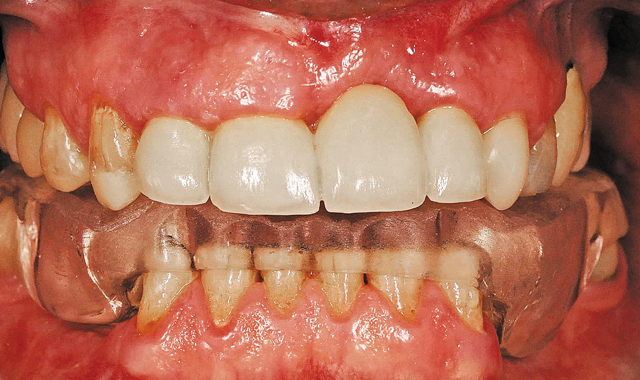

Crownwork in the posterior region.

03 The doctor then added some crownwork to the posterior region to raise the bite. As you can see from the image, this instantly made a major improvement to the overall appearance of the mouth. With this particular alteration, the patient was now on his/her way to having a normal, functional bite and a more esthetically pleasing smile (Fig. 3).